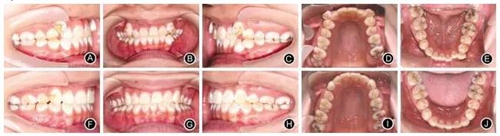

例2:患者女,18歲,要求排齊牙列,并在1年內(nèi)完成治療。臨床檢查,雙側(cè)磨牙輕度遠中關(guān)系,上牙列重度擁擠,下牙列中度擁擠,前牙Bolton比為78.12%,直面型,低角。正畸設(shè)計減數(shù)上頜兩顆第一前磨牙和左下中切牙,全口固定矯治,治療過程中調(diào)磨左下尖牙牙尖解除咬合創(chuàng)傷。固定矯治時間13個月,Hawley保持器保持,其間做牙齒美白時夜間戴用透明保持器(圖3)。

圖3典型病例2

A.治療前右側(cè)位牙合像 B.治療前正位牙合像

C.治療前左側(cè)位牙合像 D.治療前上頜口內(nèi)像

E.治療前下頜口內(nèi)像 F.治療后右側(cè)位牙合像

G.治療后正位牙合像 H.治療后左側(cè)位牙合像

I.治療后上頜口內(nèi)像 J.治療后下頜口內(nèi)像